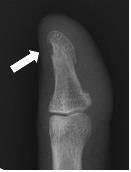

종종 종양이 있는 부위의 손발톱이 갈라지거나 변색이 되는 경우도 있지만, 육안으로는 쉽게 확인할 수 없는 경우가 많다. 종양 크기가 작아 초음파 검사로도 발견하기가 어렵고, 종양 발생 후 오랜 기간 치료가 지연된 경우 수지골의 함몰이 동반될 수 있다.

사구체 종양 치료는 종양의 위치를 정확히 파악해 수술로 제거해야 한다. 사구체종양은 보통 손톱 밑과 뼈 사이에 발생하기 때문에 수술 시 일반적으로 손톱을 들고 종양을 제거하며 수술 시간은 약 30분 정도 걸린다.

박종웅 고려대안암병원 정형외과 교수는 "사구체종양은 손에 생기는 종양의 약 1%를 차지하는 드문 양성 종양"이라며 "최근에는 정밀한 진단은 물론 사구체종양 절제술 시 가능한 한 손톱을 절개하지 않고 종양을 제거함으로써 수술 후 손톱이 갈라지는 기형을 방지하고 있다"고 말했다.